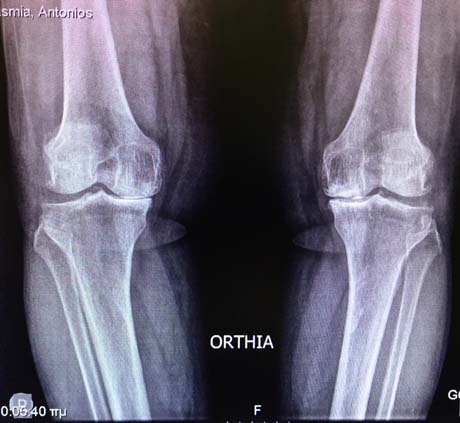

Pre-op X-rays. Severe degenerative osteoarthritis of the knees with varus deformity

Pre-op X-ray. Knees osteoarthritis

Pre-op X-ray. Osteoarthritis of the right knee

Pre-op X-ray. Knee osteoarthritis bilaterally – especially left

Pre-op X-ray. Severe knee osteoarthritis bilaterally

Pre-op X-ray. Valgus deformity of the knees